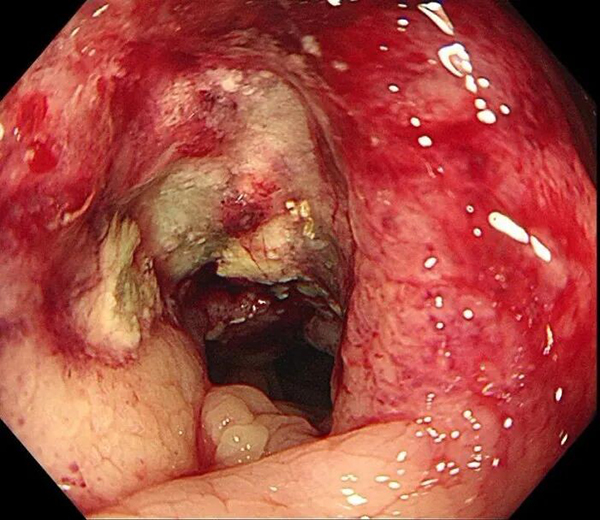

三天后,消化内镜中心孙舒仰医生操作的结肠镜顺利进行。当镜头探至升结肠近肝曲——正是之前查体摸到包块的位置时,一个不规则肿物赫然出现:它环绕肠腔2/3,表面糜烂溃疡还附着污苔,质地脆弱一碰就出血,肠壁已变得僵硬,管腔也出现偏心性狭窄,万幸肠镜还能勉强通过。“高度怀疑结肠癌。”孙舒仰医生当场判断。

几天后的病理报告印证了这一结论:中分化腺癌。“原来腹痛、大便不成型是肠腔狭窄导致的不完全性肠梗阻,进食后压力增大就疼,排便后缓解。”医生解释道。从首次就诊到病理确诊,全程仅用6天,这背后是消化内科、影像科、内镜中心、病理科的高效协同作战。目前,王女士已转至肿瘤科和普外科接受进一步治疗。